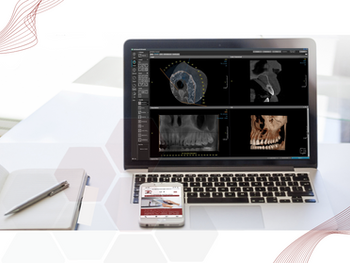

Visualize os exames online